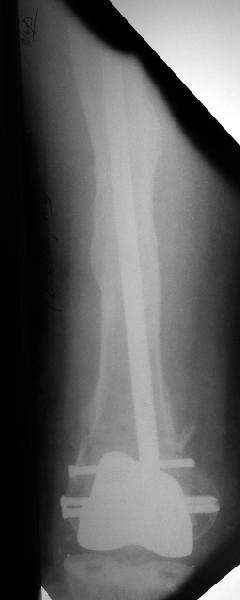

Alexander Chelnokov 02 Июнь 2004, 13:45

В итоге сделали антеградный остеосинтез. В дистракторе свежий перелом вправился сразу, а вот старый - оставил проблему, дистальный отлмомк остался все равно кзади. И гвоздь бы прошел кпереди от него, а ретроградный - перфорировал бы передний кортекс. Так что пришлось еще сделать чрескожную остеотомию через перелом, чтобы малость мобилизовать дистальный отломок. Снимки в прилжении.

Критика, комментарии, мнения?

The radiographs look excellent and a good outcome would be anticipated. The idea to osteotomize the femur shaft to compensate for the prior shaft malunion was clever and should work fine.

I can't actually see the osteotomy on either radiograph. Is it more proximal than we see in these radiographs or so well aligned as to be not visible?